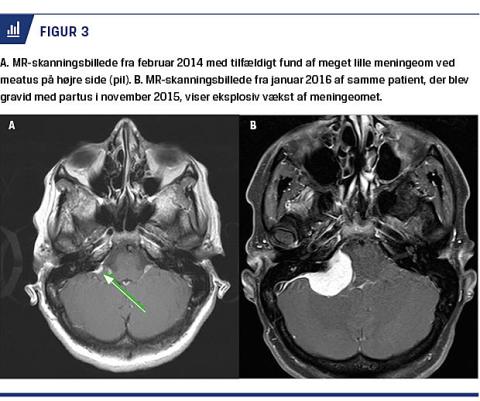

Graviditet

Eksplosiv vækst af et allerede kendt meningeom i forbindelse med graviditet eller fødsel er beskrevet kasuistisk [10]. Figur 3 viser udvikling af et sådant eksempel. I et amerikansk studie af 148 graviditetsrelaterede meningeomer (GM), fandt man, at 93% blev diagnosticeret i andet trimester eller derefter. Placeringen var signifikant anderledes end placeringen af andre meningeomer, 68% var i relation til hypofyse-sfenoid-olfactorius-regionen, og kun 34% af andre meningeomer findes her. Derfor er der også flere patienter i denne gruppe, hvor sygdommen begynder med visuelle symptomer (59%), end hos andre patienter med meningeom (25%). Årsagen til den rapide vækst af meningeomer hos enkelte i forbindelse med en graviditet er ukendt, men forklaringsforslag omfatter progesteronpåvirkning, rapid ødemdannelse inde i og omkring tumoren, glykogenophobning i tumoren og en mulig effekt af prolaktin [10].